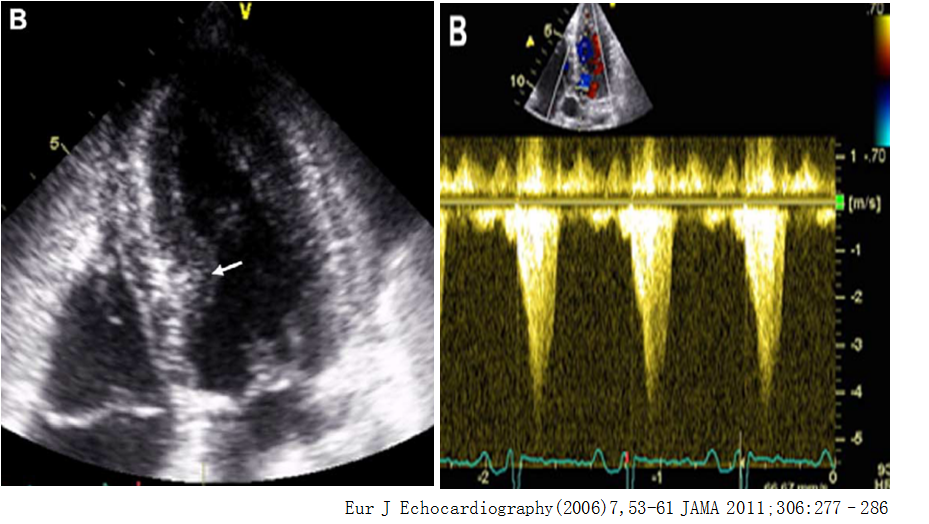

➤ TTS是一种以左心室的短暂性局部收缩功能障碍为特征的综合征,临床表现类似于心肌梗死,但冠脉造影(-),左心室收缩期心尖球形膨出,类似于“章鱼壶”的形状;而基底段心肌则代偿性收缩,甚至导致左心室流出道梗阻。

EurJ Echocardiography(2006)7,53-61

• 冠脉造影、左室造影(分型):总体分为四型,20% TTS合并左室流出道梗阻(LVOTO)